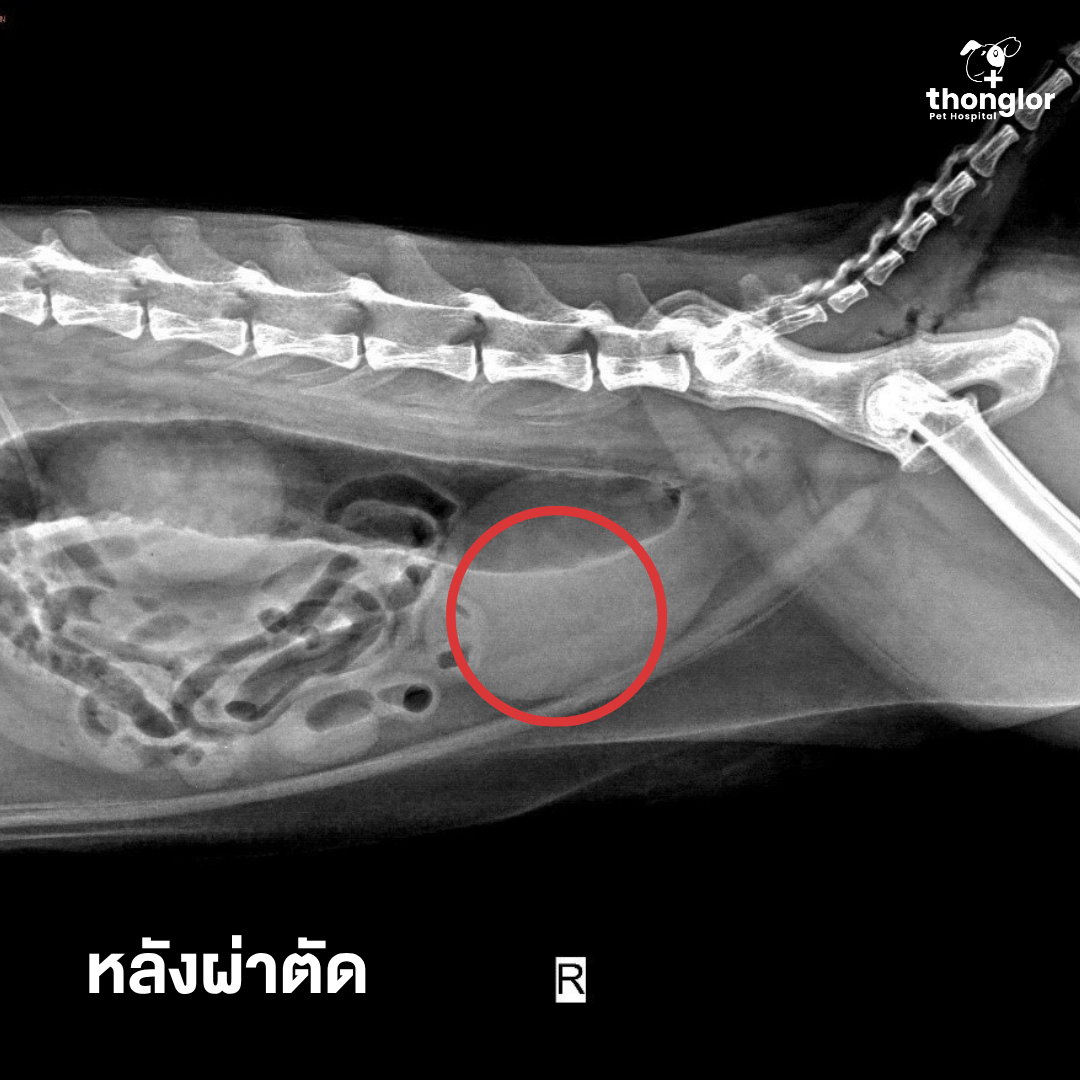

JJ the cat was brought in after showing signs of frequent litter box visits and straining to urinate but producing very little urine. After an X-ray, vets discovered 4 small bladder stones blocking the tip of his urethra

A urinary catheter was placed to relieve the blockage, and surgery was planned to remove all the stones. We’re happy to report that JJ is now fully recovered and can urinate normally again!